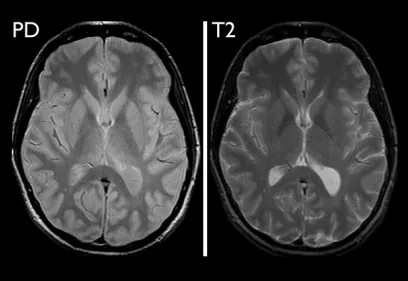

Cover image of a body scan of IMAGES magazine

IMAGES

Images is an annual publication on milestones and progress in radiology.

Read the latest issue